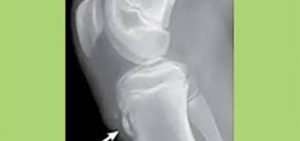

Stubborn Heel Pain

A New Approach to Heel Pain – Treating Partial Plantar[…]